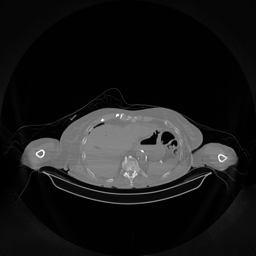

III-D Real Clinical Data Experiment

The experimental results on clinical head data are shown in Fig. 4. The reference images were reconstructed using the fast iterative shrinkage-thresholding algorithm (FISTA) with total variation regularization from non-truncated projection data. In the WCE reconstructions (Fig. 4(b)), severe truncation prevents accurate recovery of anatomical structures outside the FOV. Despite being trained solely on simulated data with a domain gap, all deep learning models can restore a substantial portion of the missing anatomy. Among them, the diffusion-based methods recover soft-tissue boundaries more faithfully than the conventional deep learning approach FBPConvNet, highlighting their stronger image generation capability. However, cDDPM reconstructions exhibit more noticeable noise than those from other methods, consistent with the simulated data results. The patchDiffusion model introduces artifacts within the FOV, likely due to its patch-wise processing strategy. While I2SB shares the same limitations as other diffusion models in perfectly restoring soft-tissue detail, it produces fewer residual noise patterns and fewer artifacts within the FOV boundaries. Overall, Fig. 4 demonstrates the strong efficacy of I2SB in reconstructing real CBCT data.